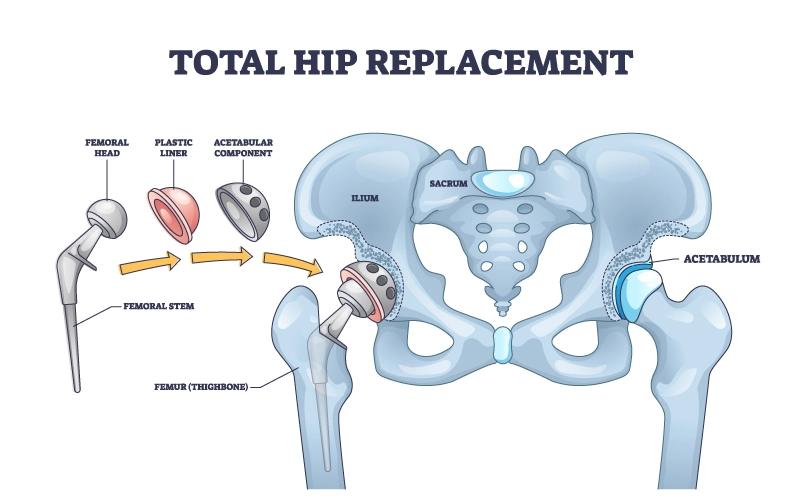

تعویض مفصل ران؛ نگاهی کلی

جراح ارتوپد با ایجاد برش، مفصل ران را نمایان کرده و بخشهای آسیبدیده استخوان ران و لگن را برمیدارد. سپس اجزای مفصل مصنوعی شامل جام لگنی، سر و ساقه فلزی در جای مناسب قرار داده میشوند.

انواع مفصل مصنوعی ران

-

سیمانی: با استفاده از سیمان استخوانی در محل ثابت میشود.

-

غیرسیمانی: استخوان بهمرور در اطراف مفصل رشد کرده و آن را محکم میکند.

-

ترکیبی: یک بخش با سیمان و بخش دیگر بدون سیمان ثابت میشود.

انتخاب نوع مفصل به سن، کیفیت استخوان و سبک زندگی بیمار بستگی دارد.